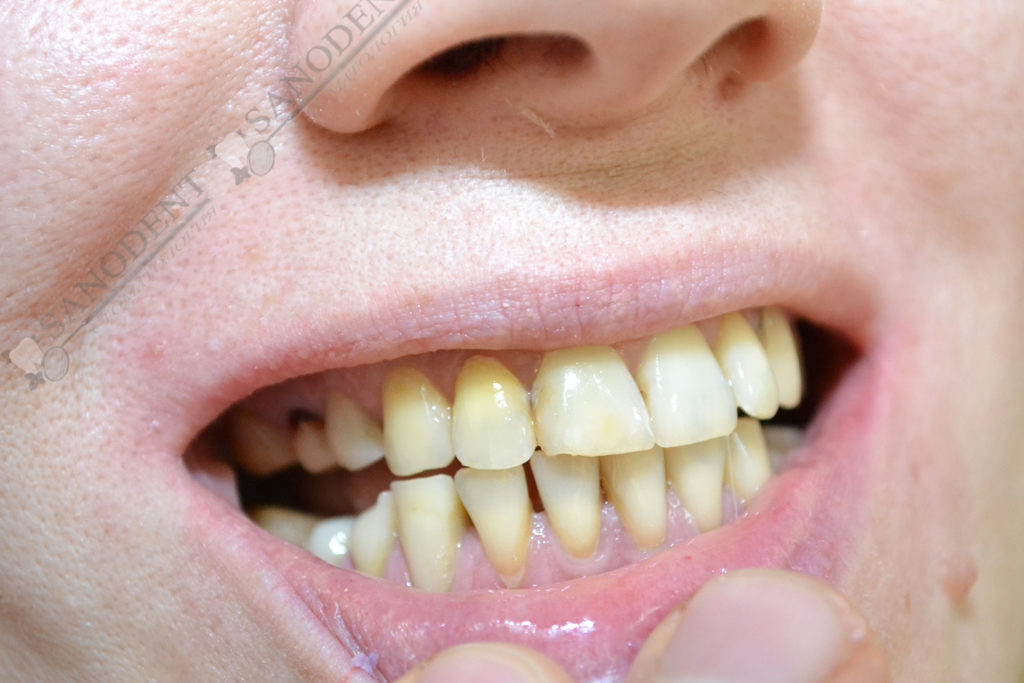

Довольно сложная работа по протезированию ввиду неправильного прикуса пациента и категорического отказа проходить ортодонтическое лечение. Проводилось формирование правильного прилегания коронок к десне . Улучшение эстетики улыбки с помощью керамических виниров.

- до лечения

- искривление зубного ряда

- многочисленные дефекты эмали